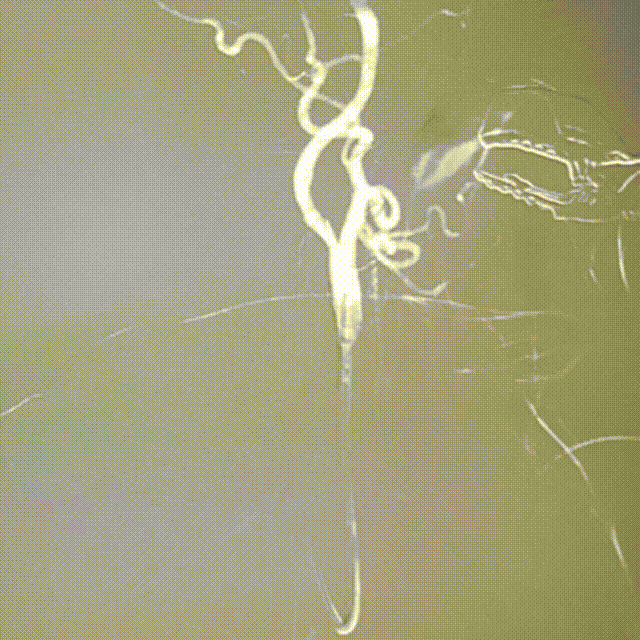

沿保护伞导丝送入支架,支架出长鞘之前将微导丝撤回,支架定位。

动脉长鞘怎么置入桡路大腔,超薄无伤 | EasyMax™ Pro长鞘经桡入路辅助行颈内动脉支架植入术_https://www.jmylbn.com_新闻资讯_第9张

释放支架。

长鞘造影显示颈内动脉C1段无明显狭窄和夹层,远端显影良好。